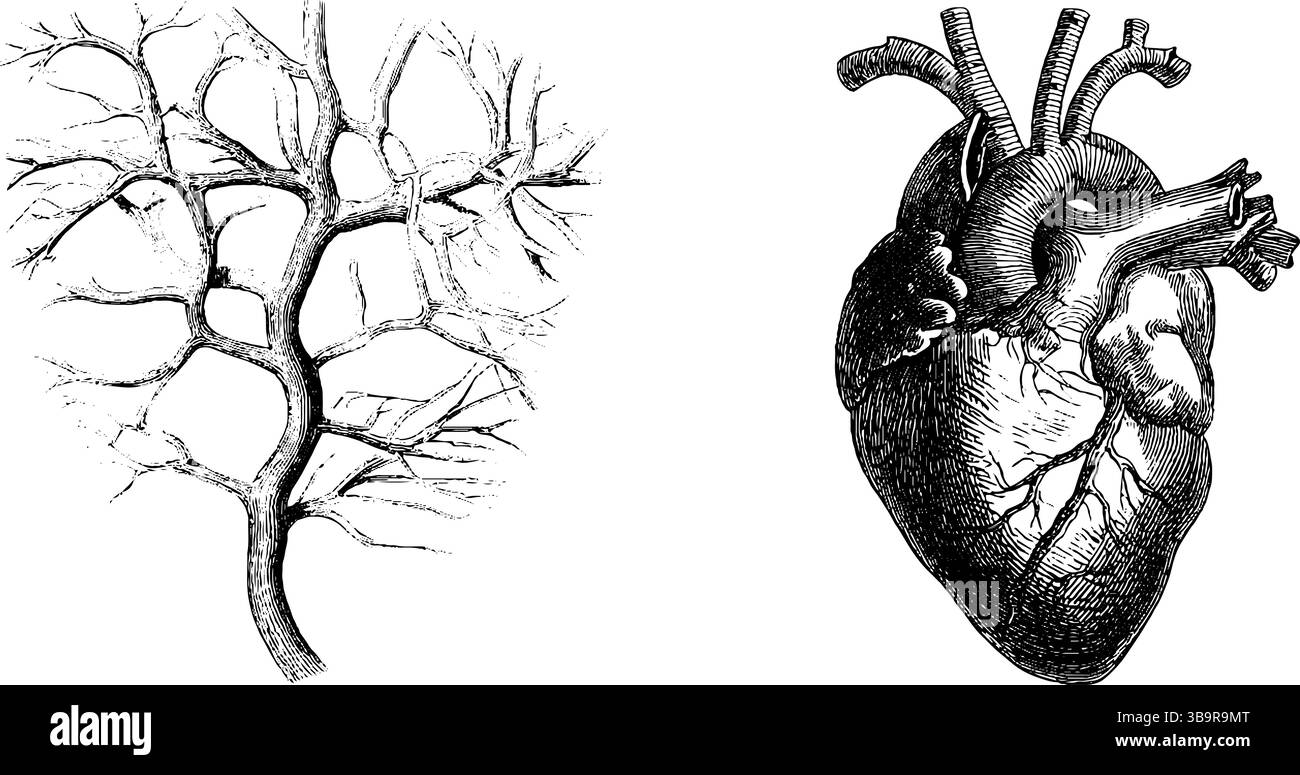

Illustration gravée vintage du réseau artériel et de l'anatomie cardiaque pour l'enseignement médical. Illustration de Vecteurhttps://www.alamyimages.fr/image-license-details/?v=1https://www.alamyimages.fr/illustration-gravee-vintage-du-reseau-arteriel-et-de-l-anatomie-cardiaque-pour-l-enseignement-medical-image677248792.html

Illustration gravée vintage du réseau artériel et de l'anatomie cardiaque pour l'enseignement médical. Illustration de Vecteurhttps://www.alamyimages.fr/image-license-details/?v=1https://www.alamyimages.fr/illustration-gravee-vintage-du-reseau-arteriel-et-de-l-anatomie-cardiaque-pour-l-enseignement-medical-image677248792.htmlRF3B9R9MT–Illustration gravée vintage du réseau artériel et de l'anatomie cardiaque pour l'enseignement médical.